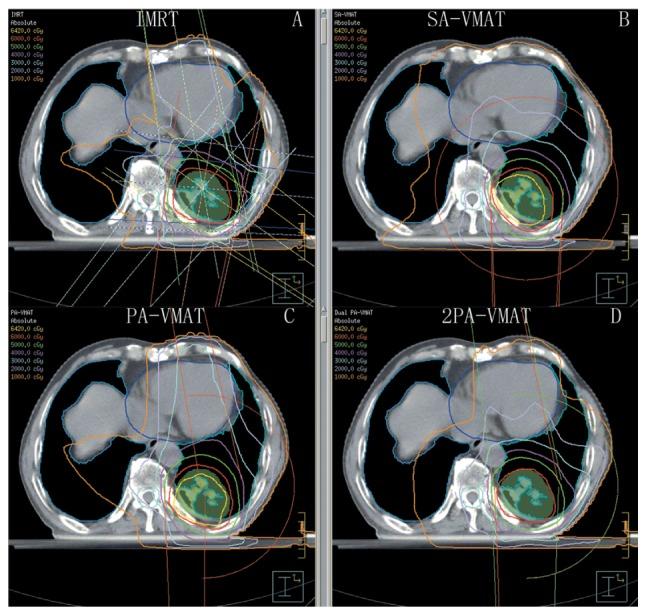

The aim of the present study was to compare intensity-modulated radiation therapy (IMRT) and volumetric modulated arc therapy (VMAT) in irradiation of lung cancer. Plans of 14 patients were compared. The results demonstrated that in peripheral lung cancer, V5 (%) of the lung in partial-arc (PA)-VMAT was decreased compared with IMRT, single-arc (SA)-, and double partial-arc (2PA)-VMAT. V30 (%) of the lung in IMRT was decreased compared with SA-, PA- and 2PA-VMAT. In the case of planning target volume (PTV) not encompassing the mediastinum in central lung cancer, the conformality index (CI) and heterogeneity index (HI) of SA-VMAT was improved compared with IMRT, PA-, and 2PA-VMAT. The received dose of heart in SA-VMAT was higher compared with IMRT, PA- and 2PA-VMAT. V30 (%) and V5 (%) of the lung in IMRT was higher compared with SA-, PA- and 2PA-VMAT; V10 (%) of the lung in 2PA was decreased compared with IMRT, SA- and PA. In the case of PTV encompassing the mediastinum in central lung cancer, the HI and CI of 2PA was improved compared with IMRT, SA- and PA-VMAT. The received dose of heart in 2PA was higher compared with IMRT, SA- and PA-VMAT. V30 (%) and V5 (%) of the lung in 2PA-VMAT was higher compared with IMRT, SA- and PA-VMAT. V20 (%) of the lung in 2PA was decreased compared with IMRT, SA- and PA-VMAT. In conclusion, it may be necessary to classify the radiotherapy plans of lung cancer into three categories including peripheral lung cancer, PTV not encompassing the mediastinum of central lung cancer, and PTV encompassing the mediastinum of central lung cancer. Each of IMRT, SA-VMAT, PA-VMAT, 2PA-VMAT strategy had individual advantages, and therefore it may be crucial to employ different planning techniques for different disease classifications and OAR requirements.

本研究的目的是比较调强放射治疗(IMRT)和容积调强弧形治疗(VMAT)在肺癌放疗中的效果。比较了14例患者的治疗计划。结果表明,在周围型肺癌中,与IMRT、单弧(SA)-VMAT和双部分弧(2PA)-VMAT相比,部分弧(PA)-VMAT中肺的V5(%)降低。与SA-VMAT、PA-VMAT和2PA-VMAT相比,IMRT中肺的V30(%)降低。在中央型肺癌中,当计划靶区(PTV)未包括纵隔时,与IMRT、PA-VMAT和2PA-VMAT相比,SA-VMAT的适形指数(CI)和不均匀性指数(HI)得到改善。与IMRT、PA-VMAT和2PA-VMAT相比,SA-VMAT中心脏接受的剂量更高。与SA-VMAT、PA-VMAT和2PA-VMAT相比,IMRT中肺的V30(%)和V5(%)更高;与IMRT、SA-VMAT和PA-VMAT相比,2PA-VMAT中肺的V10(%)降低。在中央型肺癌中,当PTV包括纵隔时,与IMRT、SA-VMAT和PA-VMAT相比,2PA-VMAT的HI和CI得到改善。与IMRT、SA-VMAT和PA-VMAT相比,2PA-VMAT中心脏接受的剂量更高。与IMRT、SA-VMAT和PA-VMAT相比,2PA-VMAT中肺的V30(%)和V5(%)更高。与IMRT、SA-VMAT和PA-VMAT相比,2PA-VMAT中肺的V20(%)降低。总之,可能有必要将肺癌的放射治疗计划分为三类,包括周围型肺癌、中央型肺癌中PTV未包括纵隔以及中央型肺癌中PTV包括纵隔。IMRT、SA-VMAT、PA-VMAT、2PA-VMAT每种策略都有各自的优势,因此针对不同的疾病分类和危及器官(OAR)要求采用不同的计划技术可能至关重要。